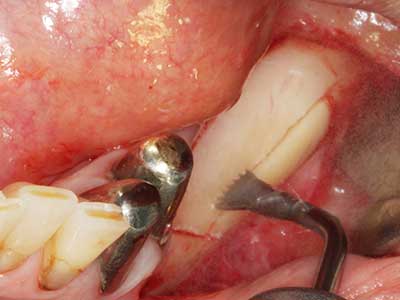

Quando le procedure chirurgiche vengono eseguite sull'osso nelle immediate vicinanze di strutture sensibili, come vasi sanguigni o nervi, gli strumenti rotanti pongono un rischio significativo di lesione iatrogena. I dispositivi piezoelettrici possono essere utili per la preparazione delle coperture ossee e la rimozione del tessuto duro in prossimità dei nervi, in particolare per la loro esposizione dopo una lesione iatrogena, ma anche durante la lateralizzazione dei nervi per le procedure di resezione e ricostruzione o il posizionamento di impianti (figg. 17-20). Il contatto leggero tra puntina piezoelettrica e nervo non causa generalmente danni, ma se si procede senza prestare attenzione con movimenti a sega o raccordi con residui di substrati ossei possono verificarsi danni al nervo temporanei o anche permanenti. Il rischio di danno, tuttavia, è considerato sostanzialmente inferiore al rischio presente utilizzando seghe o frese (Pereira, Gealh et al. 2014).